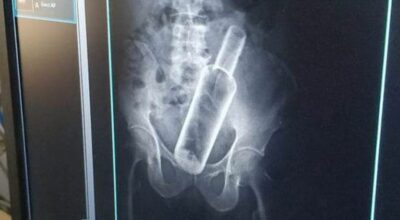

धनगढी । सेती प्रादेशिक अस्पतालमा उपचार गर्न गएका एक वृद्धको पेटमा बोतल भेटिएको छ । धनगढीको फूलबारी बस्ने ६१ वर्षीय